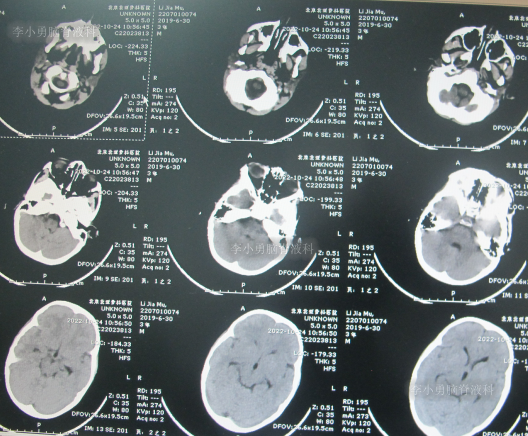

住院治疗7天即2022年5月18日,出现头痛,呕吐,体温再次升高为39.6度,心电图示室性心动过速,室早,考虑“心肌炎”,查头颅核磁(图-1)后并行腰穿见脑脊液呈金黄色,留取脑脊液送常规化验提示诊断为颅内感染,给予抗感染治疗。

图-1:2022年5月18日头颅核磁